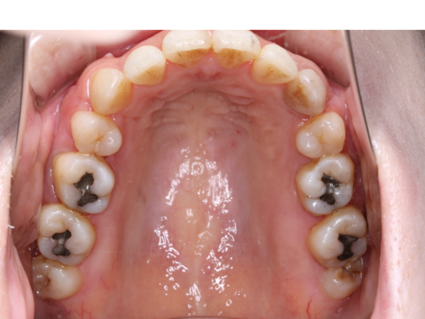

歯がデコボコに並んだ歯並びのことを「叢生(そうせい)」と言います。「乱ぐい歯」という名前でも知られています。叢生の歯並びの中で、よく知られているのが、上顎の犬歯が前方に突出している「八重歯」です。八重歯は可愛らしいイメージに捉えられることもありますが、歯並びとしては良くない、デコボコ歯並びの一種です。

叢生の原因は、顎の骨が小さく、歯が並ぶための十分なスペースが確保できないことが挙げられます。

叢生による問題は、見た目だけではありません。次のような様々な「リスク」があります。

歯並びが乱れていると、ブラッシングが難しい部分があり、汚れや歯垢が残りやすくなります。これにより、虫歯や歯周病のリスクが高まります。